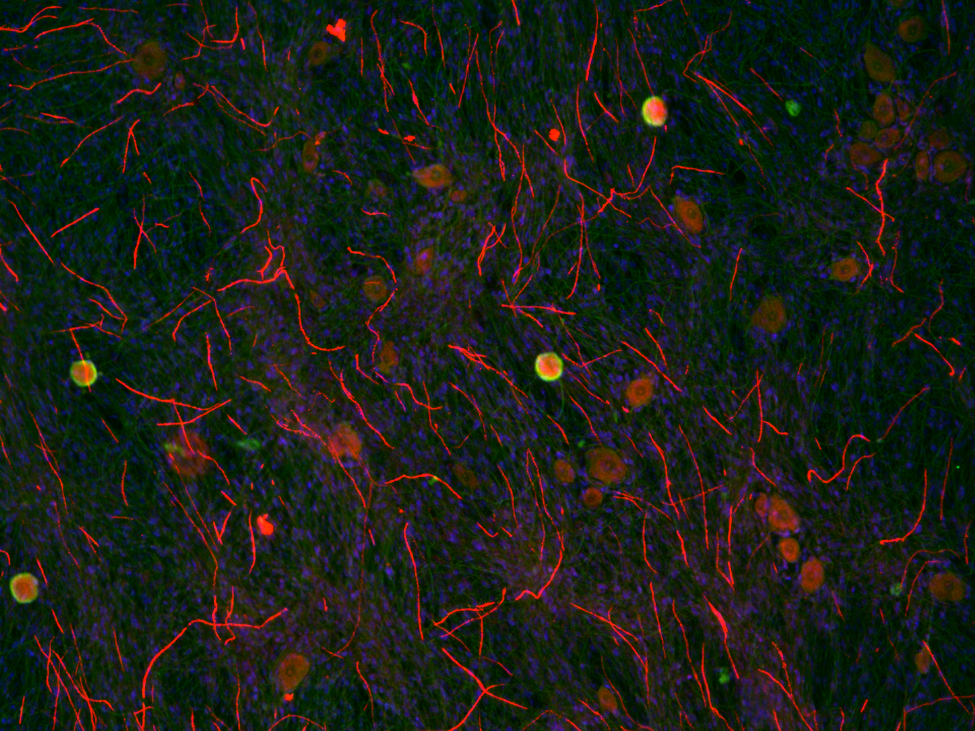

Fluorescence microscopy image of in vitro model of myelin sheath (red) formation by Schwann cells around neuronal axons (green). Cell nuclei are blue. Credit: Keit Men Wong, UB.

The research focuses on the way that cells called Schwann cells drive the formation of myelin in the nervous system. Myelin sheaths protect and insulate axons, the long nerve fibers along which impulses travel between neurons, allowing them to function properly.